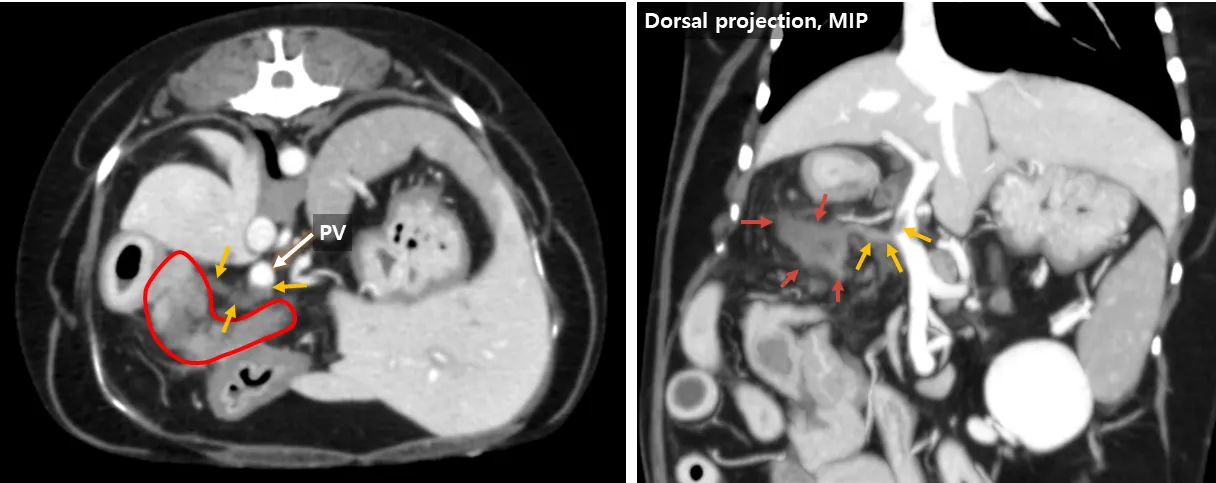

Possibly Gastroduodenal Vein Thrombosis due to Severe Pancreatitis

Summary Signalment λ₯μ€ννΈ, SF, 12y, 6.3kg CC: κ΅¬ν  Conclusion Gastroduodenal vein thrombosis Severe pancreatitis Possibly secondary fat stranding, EHBO and duodenitis Key findings μ·μ₯μ λΆκ·μΉν λ³μ°, μ’

λ, μ λ§₯ μ‘°μμ μΌλΆ μ€μ§μ μ κ°μ (red). μ λ§₯ μ‘°μμ κ°λ¬Έλ§₯ λ° μ-μμ΄μ§μ₯ μ λ§₯μ μ‘°μμ  μΆ©μ§ κ²°μ (yellow). μ·μ₯κ³Ό μΈμ ν λ³΅κ° μ§λ°©μ κ³ κ°μ (yellow) μμ΄μ§μ₯ λ²½ λΉν (mint). μ΄λ΄κ΄μ κ²½λ―Έν νμ₯ (green). μ·μ₯-μμ΄μ§μ₯ λ¦Όνμ  μ’

λ (blue). Additional findings μμΈ‘ λΆμ μ λ¨μΆ μ§κ²½ 6.3mm μμ€μΌλ‘ κ²½λ―Έν μ’

λ (bilaterally symmetric adrenomegaly) Thrombosis & Pancreatitis